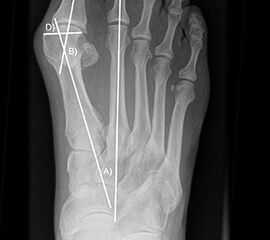

Präoperatives Röntgenbild Fuß d.p. mit eingezeichneten Winkeln. A) Intermetatarsalwinkel, B) Hallux valgus Winkel, C) Interphalangeal-Winkel.

Abbildung 2

• Operationsplanung anhand der Röntgenaufnahmen unter Beachtung wichtiger radiologischer Landmarks wie Intermetatarsalwinkel, Hallux valgus – Winkel, distaler Gelenkflächenwinkel (Distal Metatarsal Articular Angulation - DMAA), Metatarsaleindex und Sesambeinposition (Abb. 2).